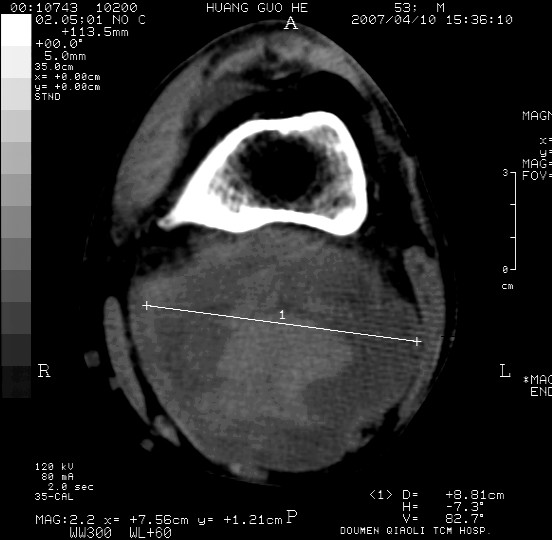

男性,左腘窝包块五个月,逐渐增大,疼痛功能受限,无发热。

查:远端血供差,质地硬。

左侧膝关节后国窝处略低密度软组织肿块,边界清楚,内见脂肪密度及高密度影.多考虑:软组织肿瘤_首选:脂肪纤维瘤.

左侧腘窝软组织肿块,边缘清晰,其内密度不均,周围骨组织无破坏,病灶增长较快,考虑:恶性病变(腘窝滑膜肉瘤可能),建议穿刺活检。